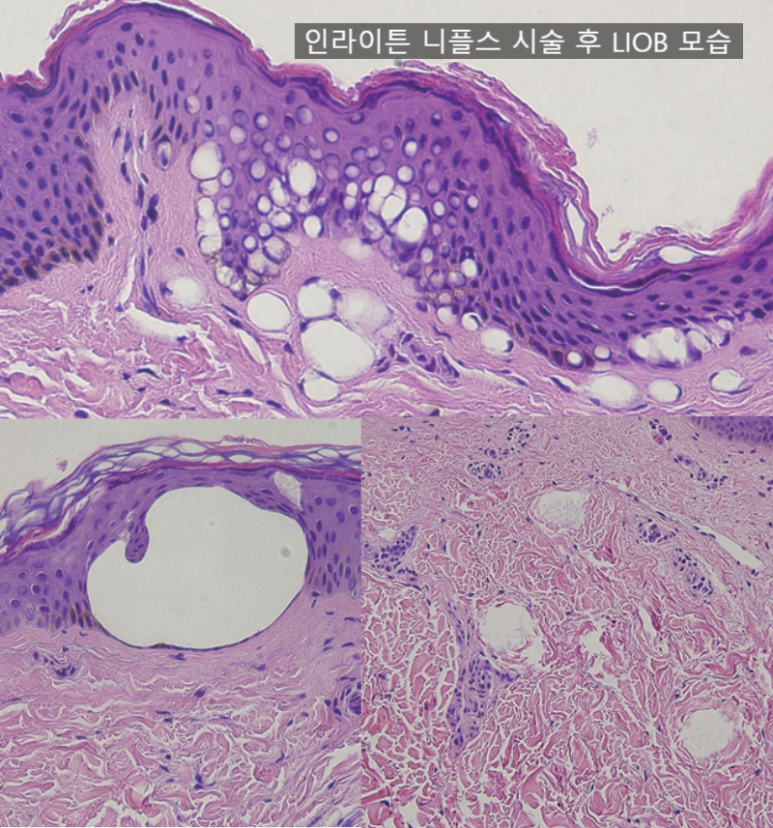

피코 레이저로 눈가 주름을 치료할 수 있는 원리는 바로 피코 레이저의 'LIOB(Laser Induced Optical Breakdown)' 현상에 있습니다.

LIOB란, 높은 에너지로 인해 플라즈마 효과가 발생해 공동화 현상을 만들어 피부의 새 조직이 차오르도록 만드는 효과입니다.

위 조직학 사진을 보면, 피부 조직 곳곳에 하얗게 구멍이 뚫려 있는 것이 보이죠? 이 공간이 시간이 지나면 피부 재생 반응이 일어나며 새 조직으로 채워지게 됩니다.

이런 과정이 반복되면서 흉터, 모공, 주름 등과 같이 움푹 패인 피부가 새롭게 차오르는 것이죠.